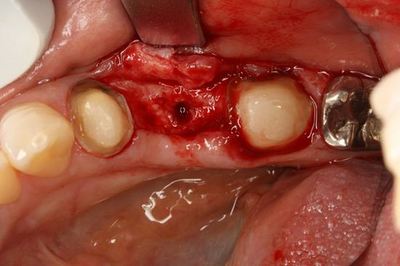

ここからは粘膜を剥離して実際の歯槽骨を見ながらドリリングします。